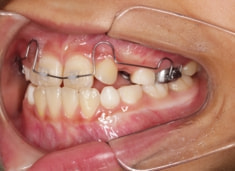

治療前

治療開始時

FX(フェイシャルアキシス)は85度なので東洋人の平均値に近く、下顎が前方に過剰成長するリスクは強くはありません。

しかしやはり上顎は劣成長で、下顎が優位な状態ではあります。

上下顎のギャップはありますが、顔面自体の幅径は良好な値を示していますので、スペース不足は拡大することによって解決できポテンシャルはあると考えられます。

左右の非対称もさほど強くありません。